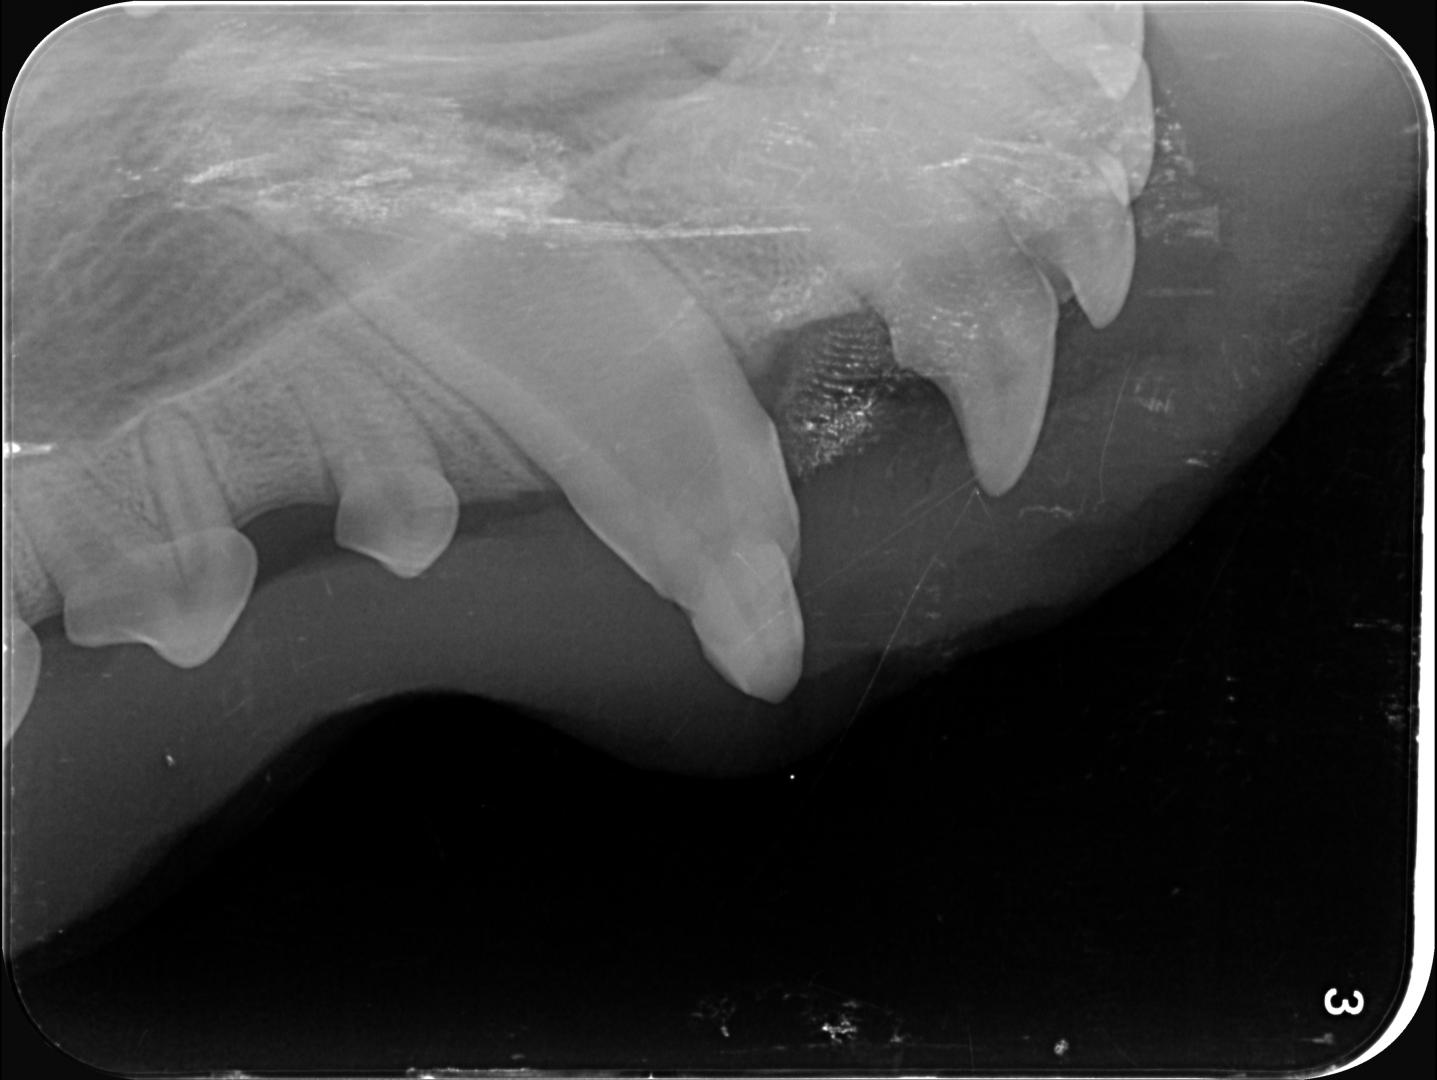

radio croc

Dans le cas d'Alphonse :

- l'apex est fermé (cercle vert) sur les 3 dents concernées ; aucun abcès n'est visible et donc la pulpe ne présente pas de signe de contamination (vérifié également par sondage, le canal n'est pas perméable)

- La couche de dentine semble déjà conséquente et suffisante pour donner une chance à la dent (trait bleu) ;

La décision est donc prise de tenter de la conserver, et de protéger la pulpe en déposant une couche de résine pour combler les surfaces abîmées du croc.